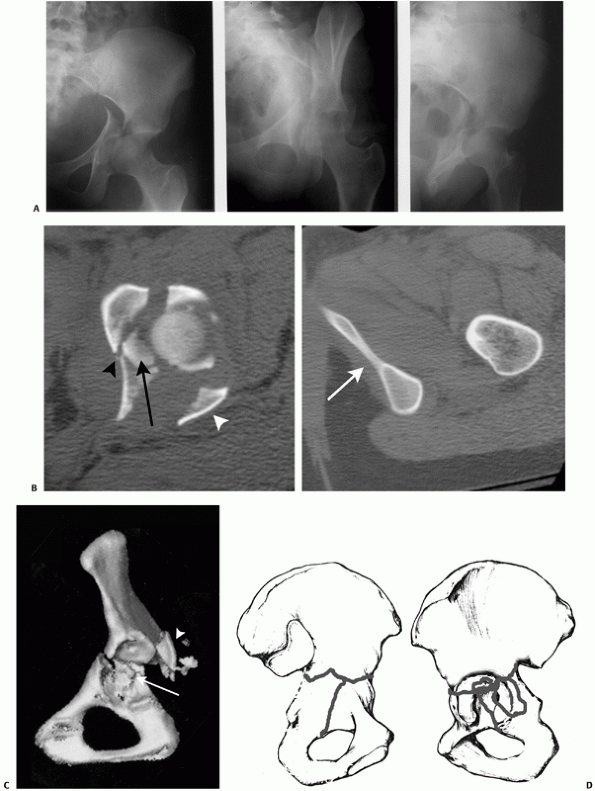

FIGURE 45-5 An 18-year-old 390-pound man (A) was involved in a motor vehicle accident. Anteroposterior radiograph (B) of the hip and selected two-dimensional computed tomography section (C) show a T-type fracture of the acetabulum and an ipsilateral fracture of the femoral shaft (D). Retrograde nailing was used to stabilize the femur (E) followed by acetabular fixation 2 days later (F) using the Kocher-Langenbeck approach. (Copyright Berton R. Moed, MD.)

treatment method should be selected, such as retrograde nailing (Fig. 45-5). When the femoral shaft and acetabular fractures are addressed as se

quential procedures during the same anesthesia, antegrade femoral

nailing still may not be the best choice. Compromised access to the

proximal femur, which may occur with a severely displaced associated

both-column fracture, or an irreducible dislocation of the femoral head

that precludes satisfactory femoral shaft fracture reduction are two

such situations. Alternatives include plating or retrograde nailing.